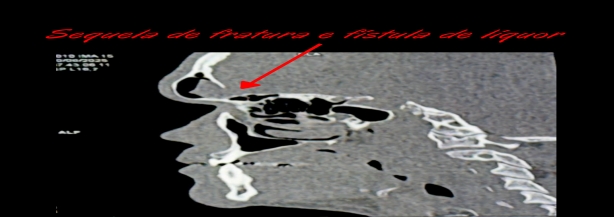

Dentre estas, cito as hidrocefalias pós-traumáticas, fístulas e líquor (líquido que fica dentro do crânio e coluna), alterações infecciosas e deformidades da região do crânio e face.